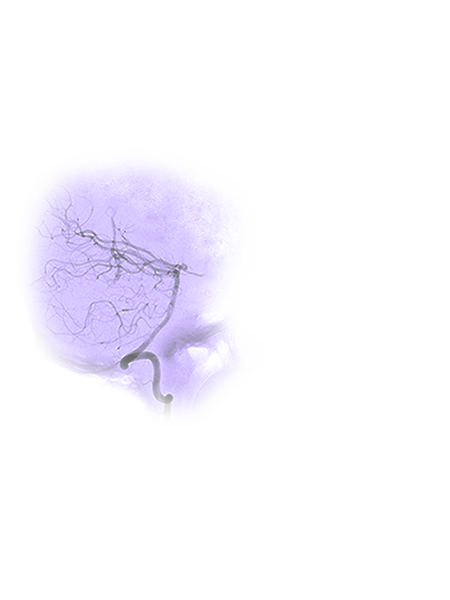

After looking deeper into Terrah’s imaging, her neurointerventional radiology team identified a major complication. Traditionally, to treat an AVM, a neurosurgeon would surgically remove it or enter the blood vessel to embolize it, or seal it, with a special glue-like material. But Terrah’s AVM was located in a part of her brain that would be difficult to access through traditional approaches because her team would need to work against the flow of blood. They would need to stop her heart, stemming blood flow to her brain, in order to travel upstream and reach the abnormality.

Terrah had a posterior circulation AVM in what is called the eloquent cortex — a part of the brain that controls vital functions such as speech, movement and sensation. Removing her AVM through open brain surgery was possible, but presented a substantial surgical challenge: She faced the risk of serious side effects, ranging from paralysis to cranial nerve injury.

With Terrah’s circulation slowed to a standstill, Dr. Jahromi guided a catheter through Terrah’s artery in the opposite direction of blood flow, essentially the inverse of a conventional procedure. Had there been circulation in the brain, the catheter would have been pushed back by onrushing blood.

After 12 stops and starts of Terrah’s heart, Dr. Jahromi was successfully able to embolize the pressurized vein with medical glue and eliminate Terrah’s AVM. After years of living with a ticking time bomb in her brain, Terrah had been healed by her team’s careful measure of minutes and seconds.